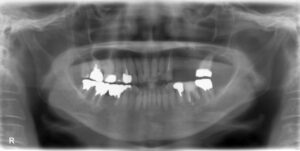

上顎大臼歯1本欠損症例

BEFORE AFTER 31歳女性/上1本欠損/インプラント埋込手術 【治療内容】 左上第一大臼歯の虫歯が大きく進み、…